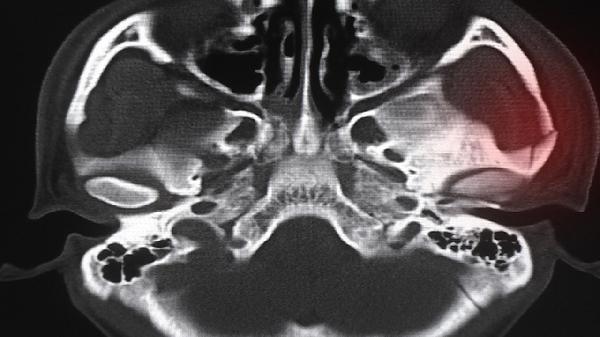

5、医学干预

对于病理性生长迟缓,医生可能建议重组人生长激素注射液治疗。严重骨骺早闭病例或考虑肢体延长术,但需严格评估手术风险。所有医疗措施必须在内分泌科医生监督下进行,禁止自行使用增高类药物。